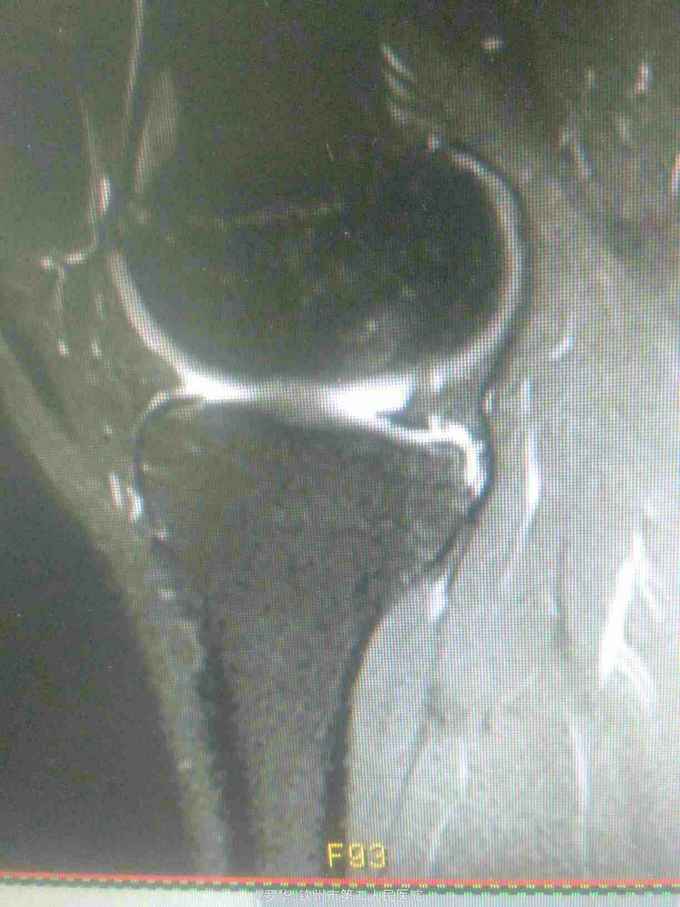

主诉:扭伤致左膝关节活动受限3月余。病史:患者男性,31岁,于入院3月余前扭伤左膝关节,致左膝关节肿痛、活动受限,尚可站立行走,但不能剧烈运动及重体力劳动,曾行磁共振检查提示左膝前交叉韧带损伤,半月板损伤,现为进上一步治疗入院。

查体:左膝关节无明显压痛,前抽屉试验阳性,侧方应力试验、麦氏征、研磨试验均阴性,膝关节屈伸活动可,余查体未见特殊。 辅查:膝关节磁共振提示左前交叉韧带损伤,左膝关节半月板损伤。

诊断:左膝关节前交叉韧带断裂,左膝关节半月板损伤。 治疗:予硬外麻下行左膝关节前交叉韧带重建术。